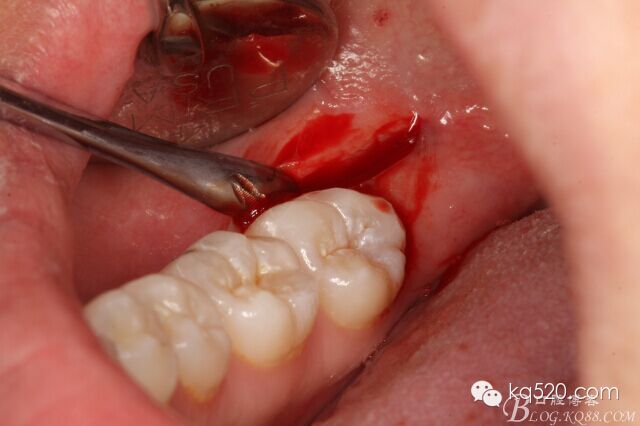

圖5.偏頰側(cè)、做直線微切口,切口約1cm。

圖6.翻小瓣

圖7.暴露48合面

圖8.小牙挺挺松48.